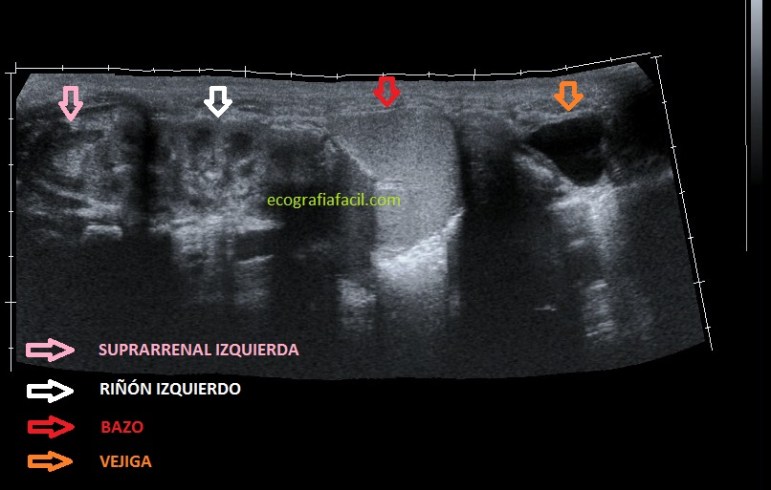

No es necesario recordar la anatomía a estas alturas, ni su localización, solo quiero que veas la imagen siguiente:

It is not necessary to remember the anatomy at this point, nor its location, I just want you to see the following image:

De esta manera conseguí la imagen que tienes ante ti, mira y compara con la anatomía normal, observa la Suprarrenal, hipoecogénica en forma de boomerang, después el Riñón Izquierdo donde podemos ver nítidamente un corte longitudinal con ambos polos, inmediatamente distal el Bazo, y después la forma anecoica de la Vejiga.

In this way I got the image that you have before you, look and compare with the normal anatomy, observe the adrenal, hypoechoic in the form of a boomerang, then the left kidney where we can clearly see a longitudinal section with both poles, immediately distal the spleen, and then the anechoic form of the bladder.